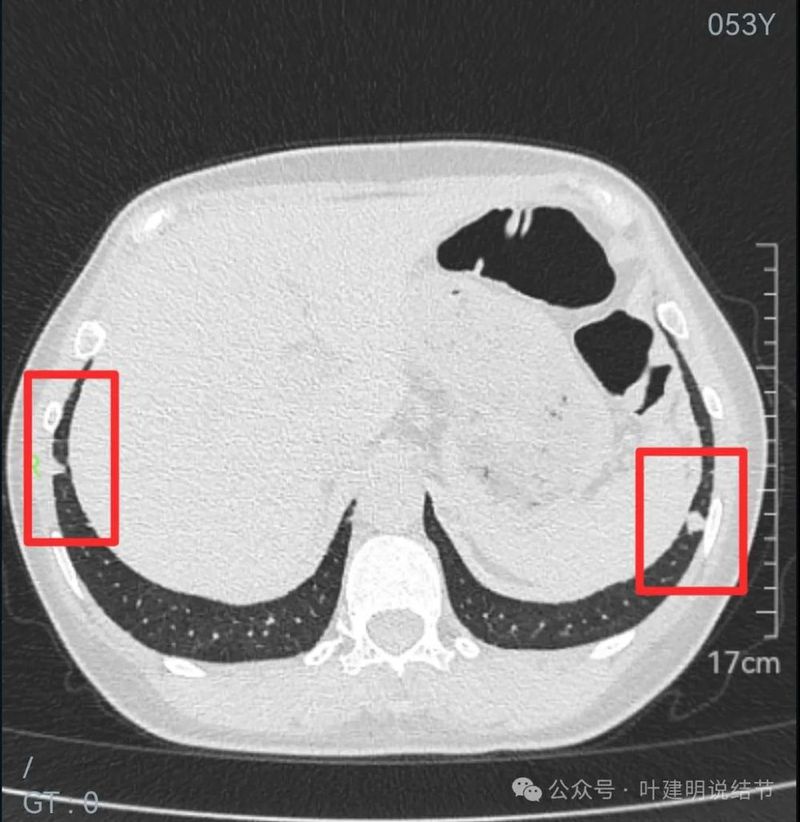

两下肺实性结节,边缘平直,右侧的以宽的基底与胸膜侧接触,两侧均无收缩力,也无膨胀感。考虑良性结节(与之前对比也无进展)。